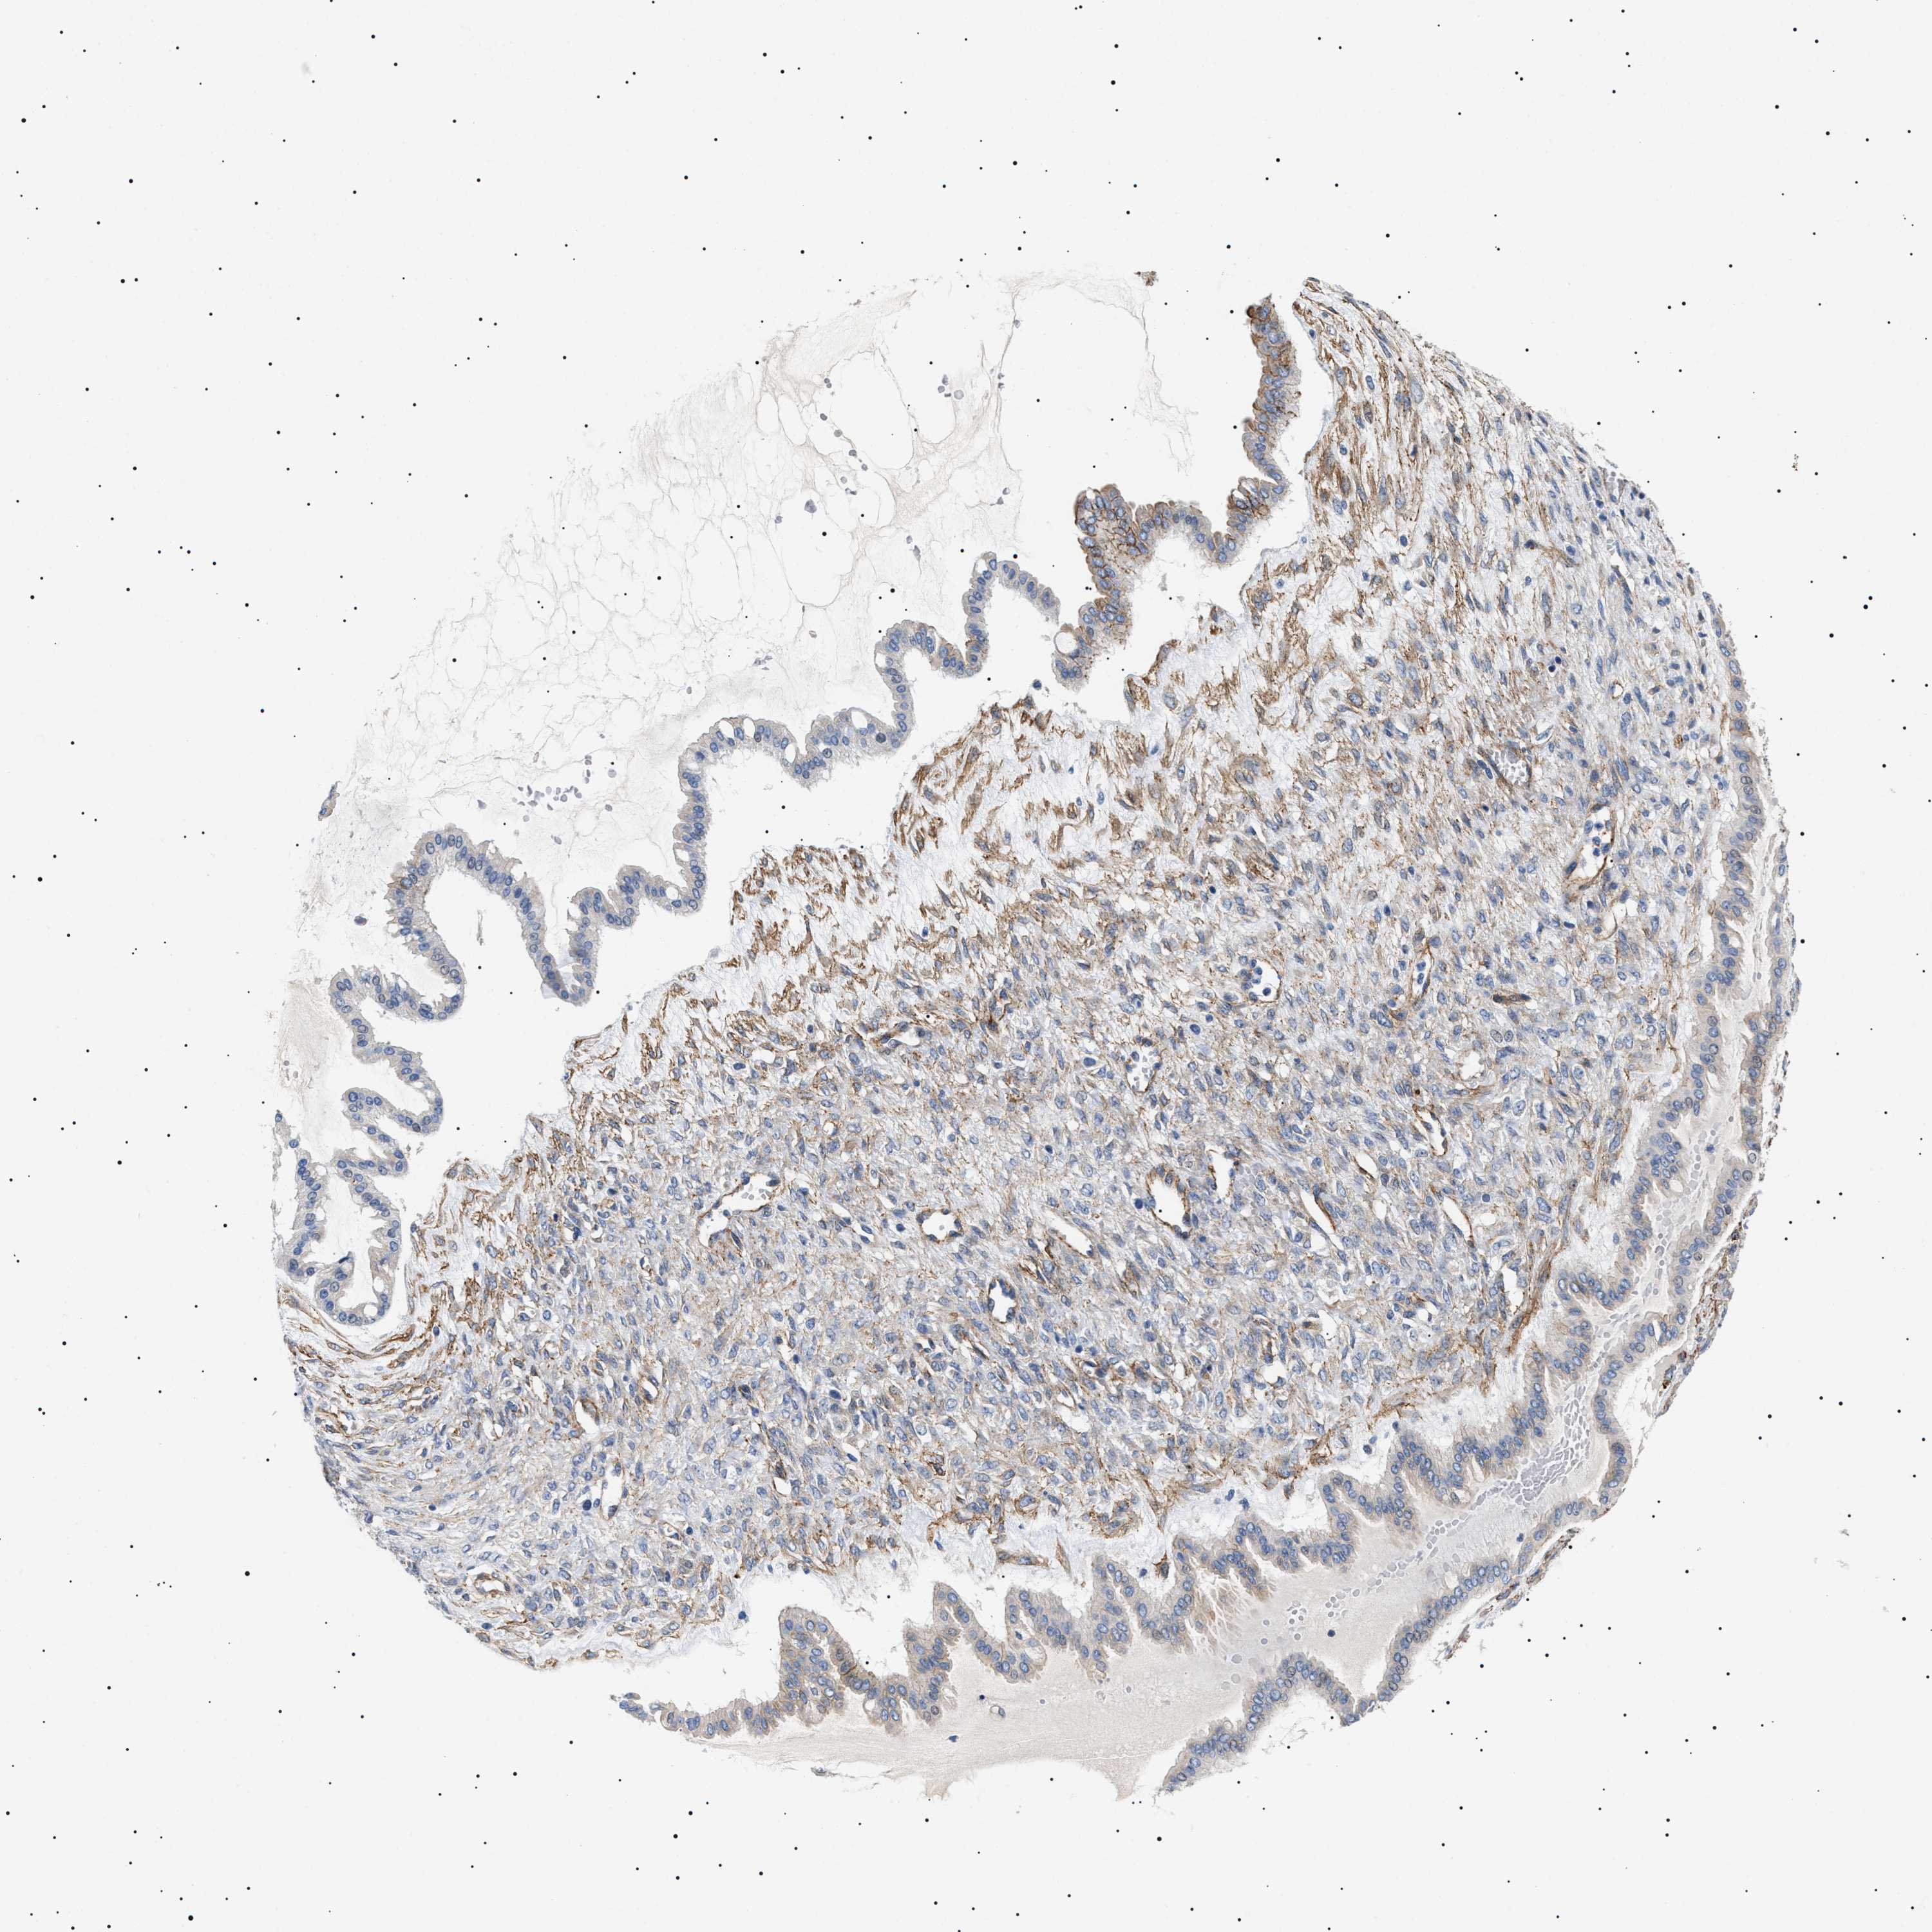

OVARIAN CANCER - Protein expressioni

A mouse-over function shows sample information and annotation data. Click on an image to view it in a full screen mode. Samples can be filtered based on level of antibody staining by selecting one or several of the following categories: high, medium, low and not detected. The assay and annotation is described here.

Note that samples used for immunohistochemistry by the Human Protein Atlas do not correspond to samples in the TCGA dataset.

Antibody stainingi

Antibody staining in the annotated cell types in the current human tissue is reported as not detected, low, medium, or high, based on conventional immunohistochemistry profiling in selected tissues. This score is based on the combination of the staining intensity and fraction of stained cells.

Each image is clickable and will lead to virtual microscopy that enables deeper exploration of all samples and also displays staining intensity scores, fraction scores and subcellular localization as well as patient and tissue information for each sample.

Antibody HPA016579

Antibody HPA059374

Cystadenocarcinoma, serous, NOS

Carcinoma, endometroid

Cystadenocarcinoma, mucinous, NOS

Carcinoma, NOS